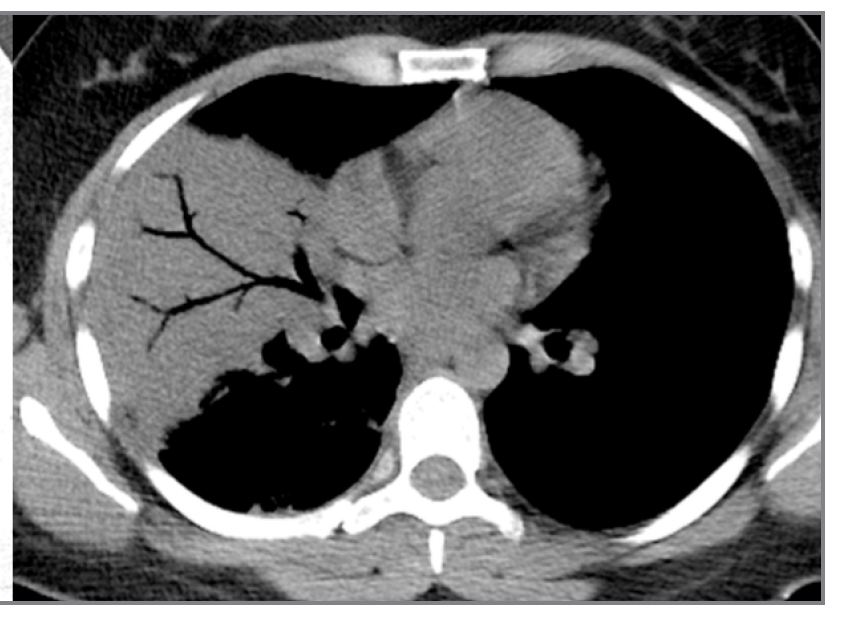

What is this?

IMH

aortic dissection

Aortic Aneurysm